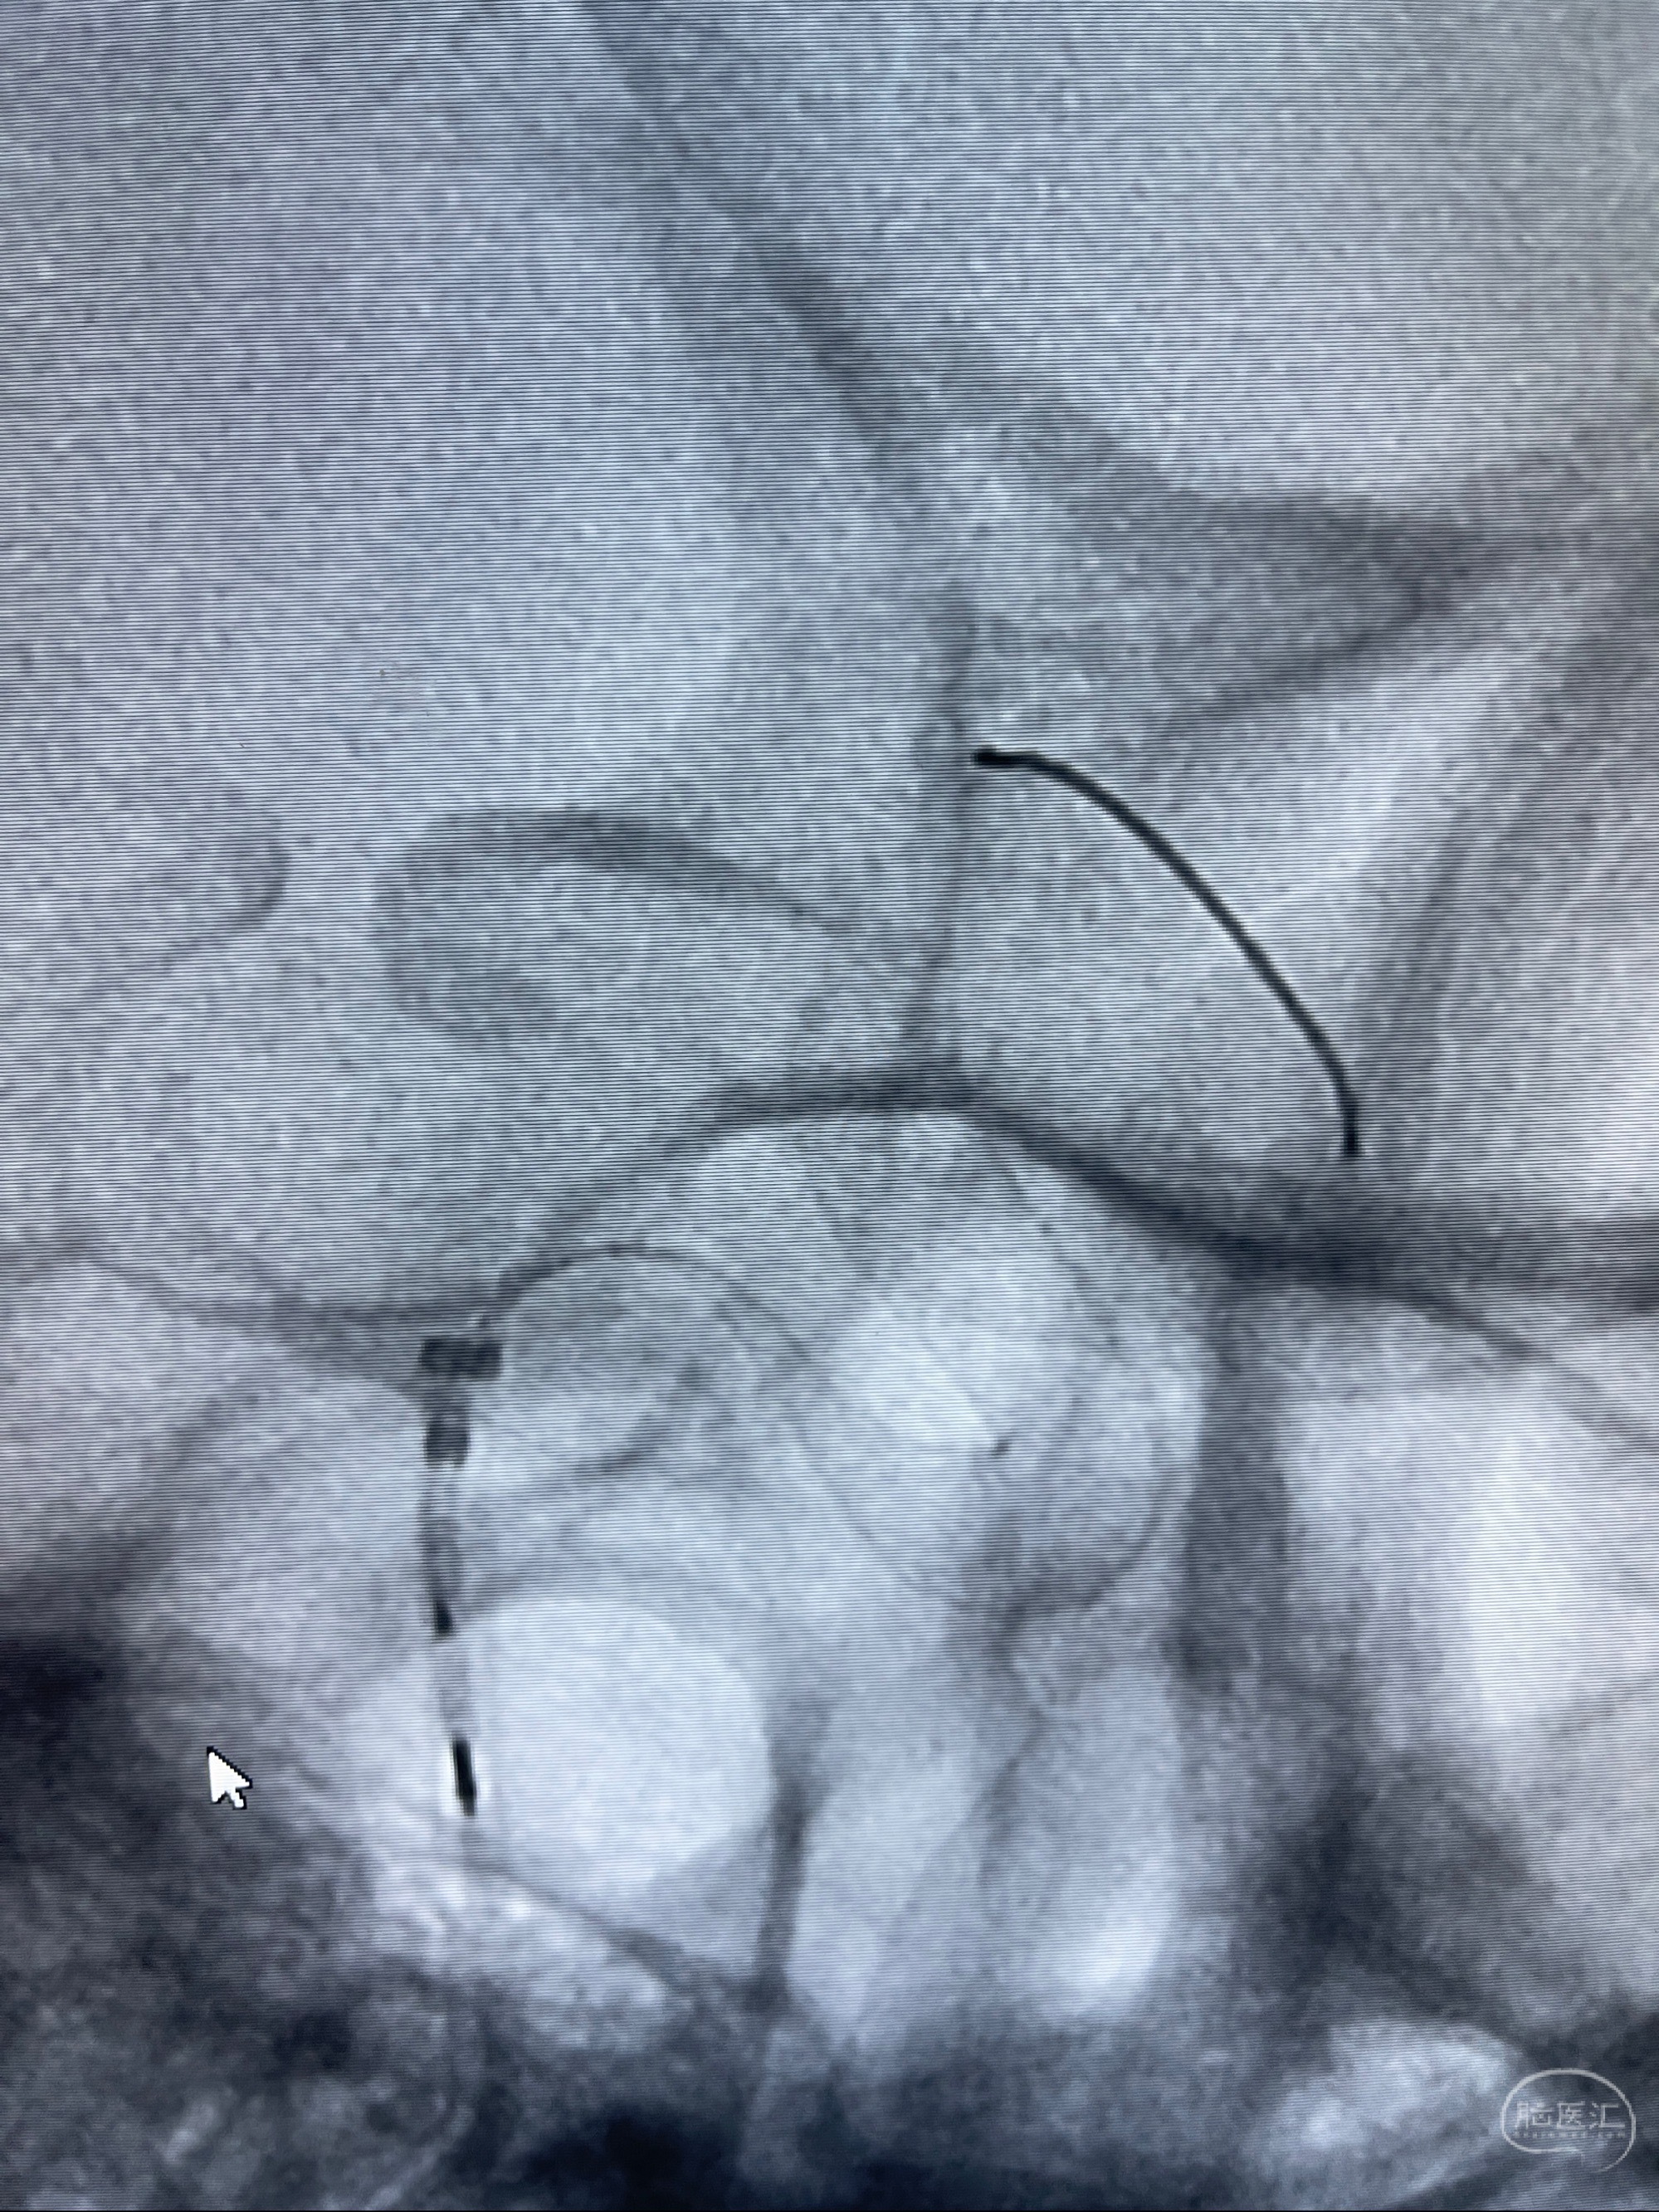

2023-07-27全脑血管造影:双侧颈内动脉眼动脉段动脉瘤,右侧较大

2023-08-01全麻下行双侧颈眼动脉瘤支架辅助栓塞

- pipeling4.5-20mm

- pipeline 4.0-20mm